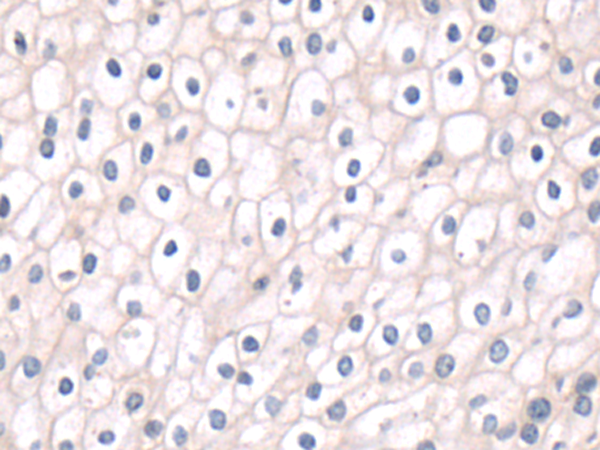

分类: 科研抗体货号: P11050别名:应用: IHC反应种属: Human